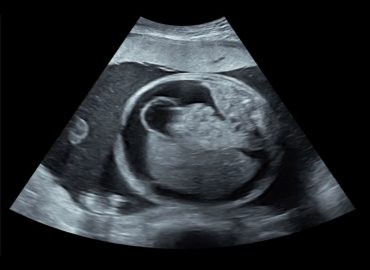

Embarazo de 26,2 semanas. MC Genitorragia

Escasa ganancia ponderal. Crisis de cianosis generalizada